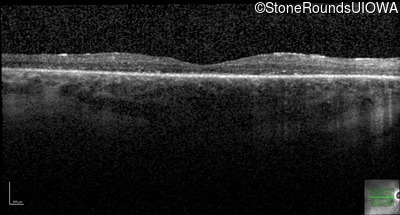

Optical Coherence Tomography - Right - 20/50

Exemplar / OCT Stack

OCT Stack